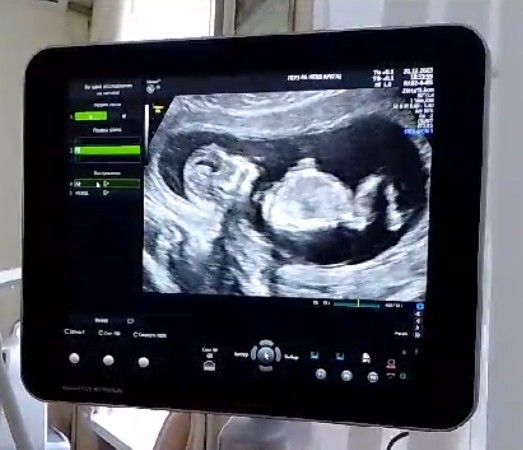

Пол ребенка по УЗИ в 12.5 недель сказали с большой вероятностью мальчик, кто разбираеться в половых бугорках

Ой какой перец деловой 😅 фотка классная! Грудь колесом, спинка ровная, как будто шляпа на груди, ну джентльмен 😁